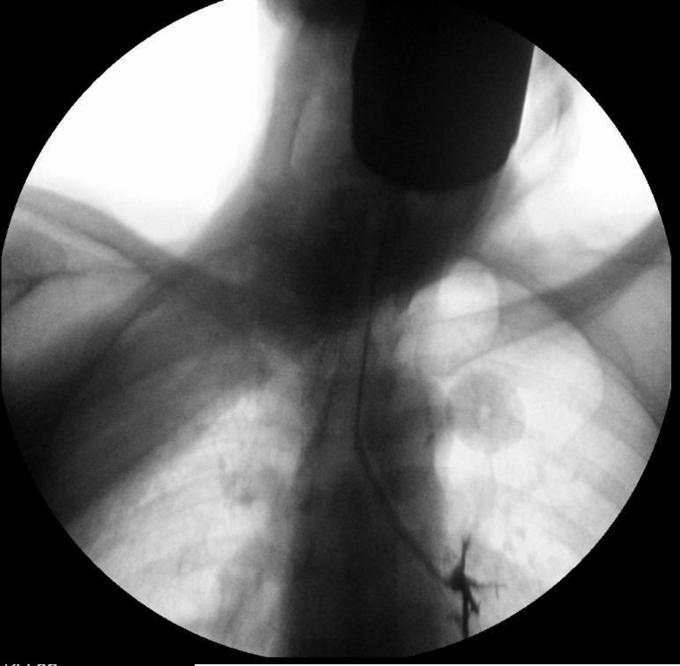

钡餐误吸

吞咽困难查因 安排吞钡试验

患者白日行钡餐检查,夜间出现呼吸困难,血氧饱和度下降,考虑存在1型呼吸衰竭 讨论: 1.目前针对钡餐误吸性肺炎的治疗措施哪些有意? 2.如何预防本次事件?